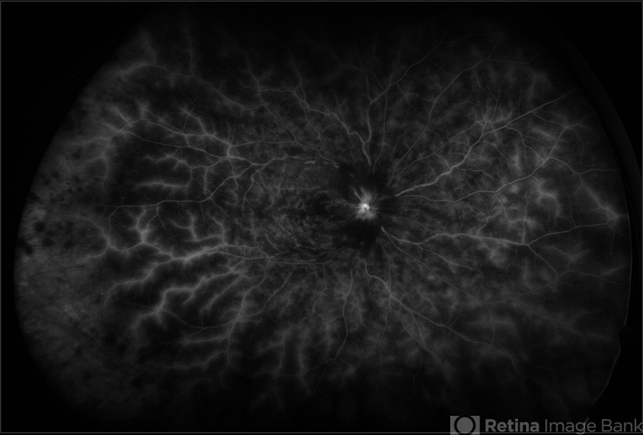

- central retinal vein occlusion (CRVO), fluorescein leakage, fluorescein angiogram (FA), ultra-wide field imaging, Optos, hemorrhage

Optos - Description

- Ultra-wide field fluorescein angiogram of a patient presenting with a central retinal vein occlusion their right eye.